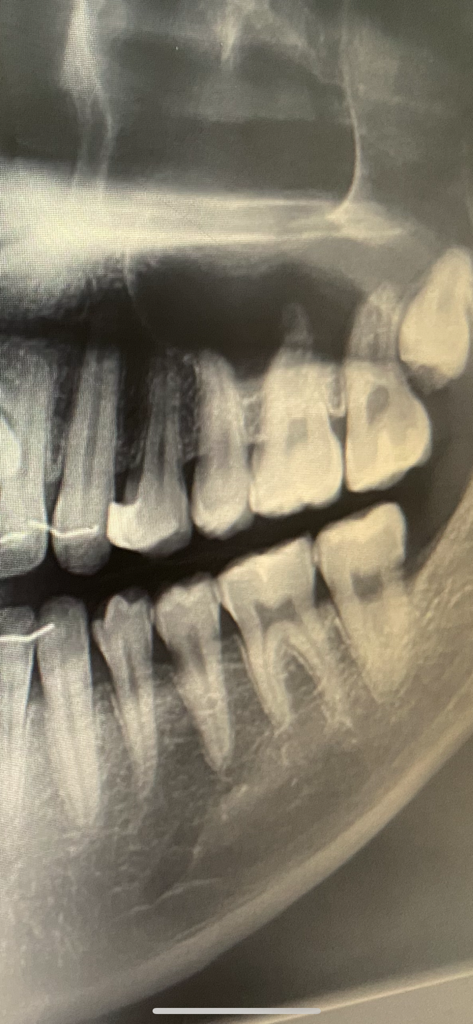

치과를 가야 하는데 엑스레이 보는 법을 알려주세요.

아래 두번째 어금니 문제로 치과를 가야 합니다.

이전에 충치가 생겨 레진으로 때웠던 기억이 있는데

단순히 때우기만 한 것인지, 인레이로 한 것인지 기억이 잘 나지 않네요.

다행히 엑스레이가 있긴 한데 보는 방법을 모르겠어요.

그리고 저 부위에 약간 단차? 같은 것이 느껴져서 치과를 가려 하는데 가면 충치치료를 다시 받게 될까요?

엑스레이 상에서 보면 인레이로 하신건 아닌거 같습니다. 가장 뒤치아는 인레이로 햇을 가능성이 잇습니다. 엑스레이 상태로만 본다면 치아의 씹는면이 교모가 된거 같으니 치과에 가셔서 검진을 받아보세요.